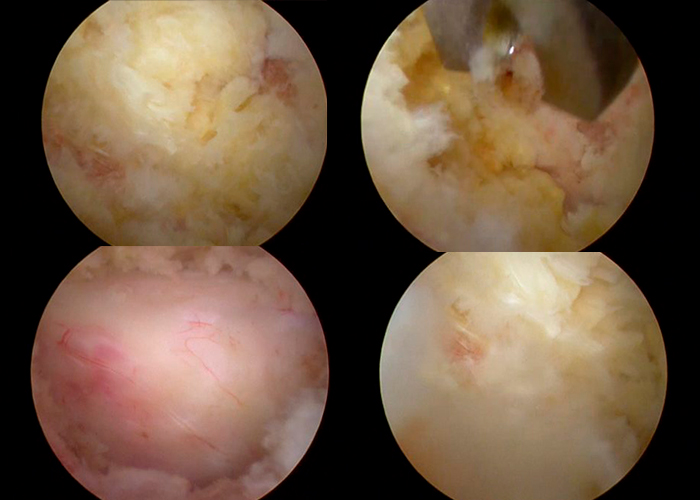

Operación

Se le coloca Membrana para proteger la dura madre Duragen.